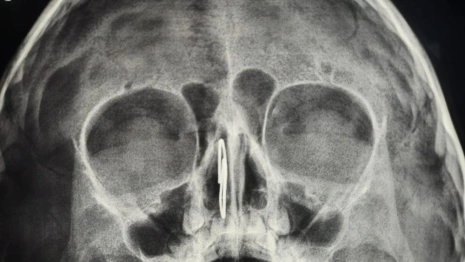

Владимирские врачи успешно удалили скрепку из носа 4-летнего малыша. Об этом сообщила пресс-служба ОДКБ в четверг, 11 сентября.